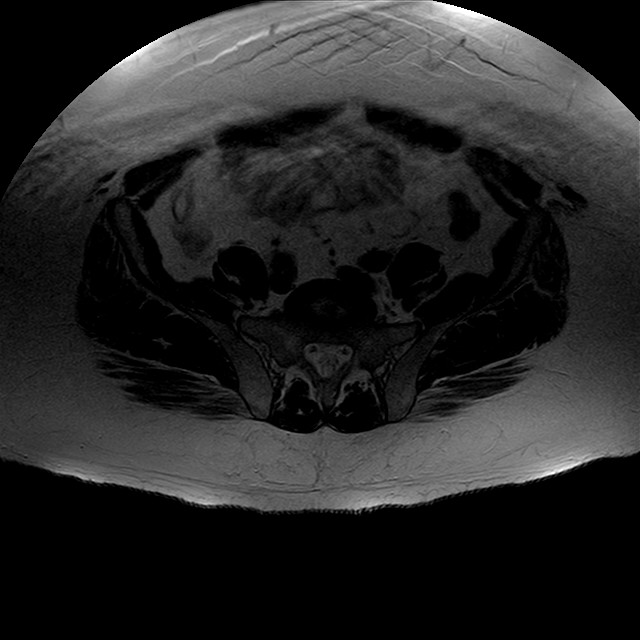

Esami: RMN BACINO

eT2w TSE

Evidenti e simmetriche alterazioni osteofitosiche in regione coxo femorale con riduzione delle rime articolari. Degenerazione completa del cercine glenoideo. Non attuali segni di versamento articolare. Non segni di edema osseo che escludono attuale algodistrofia od osteonecrosi. Lieve e simmetrica riduzione del trofismo della muscolatura glutea.